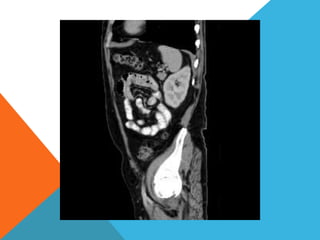

El paciente presentó síntomas de sangrado digestivo y pérdida de peso. Exámenes revelaron gastritis crónica asociada a H. pylori. Un tumor fue descubierto en una colonoscopia normal. La cirugía removió un tumor fibroide solitario, una rara neoplasia mesenquimal que usualmente crece lento y tiene bajo potencial de malignidad. El pronóstico después de la remoción quirúrgica es generalmente bueno.